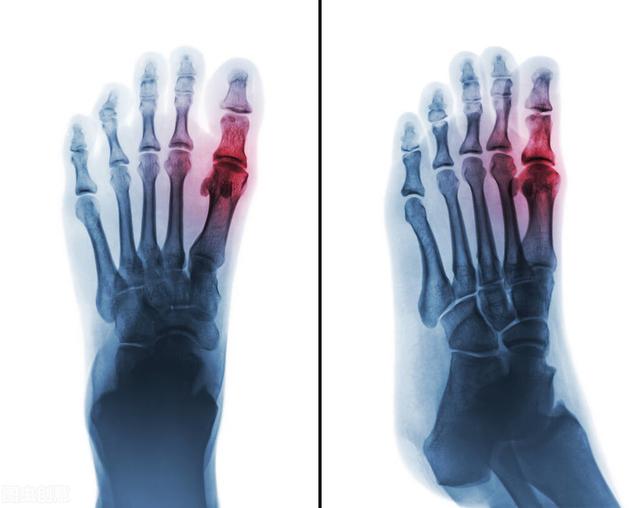

その子の両親によると、この子の外反母趾はひねってから痛み出したという。診察してみると、この子の外反母趾は特に腫れていて、上の写真よりもずっと腫れていた。その時は、どう見ても捻挫による腫れには見えなかった。

答えは私の推測通りだった。この子の両親は火鍋店を経営しており、家族はほとんど毎日火鍋を食べ、特に内臓のような翌日には腐敗が心配される食材は、この子も毎日食べている。慌てて子供の尿酸値を調べたら、なんと800umol/l。。

まず、痛風はプリン体の代謝異常によって尿酸が異常になり、関節に尿酸が沈着して尿酸塩結晶を形成し、それが局所の炎症を誘発し、組織の破壊を引き起こし、痛みを誘発する。だから痛風の発症は尿酸の異常と密接な関係がある。

実際には、それは体内の尿酸の沈着の多量は、特に骨の関節に沈着し、体から排出することができない、いくつかの関節を動かすのは簡単です。尿酸沈着は、抵抗上の白血球の数が多い、それは痛み、赤みや腫れとして現れる炎症を生成します。ひどい場合には、歩くことができなくなり、痛風結石が形成されることさえある。